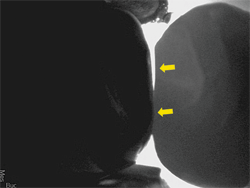

Identifying decay, especially the interproximal type, can be challenging. It is not enough just to be aware of a cavity between teeth; with a CariVu image, I can see if the cavity is more toward the buccal or lingual. This helps me to plan my approach to restorative treatment. For an even more distinctive image, I turn on the Spotlight tool in DEXIS™ Imaging Suite software, which enhances the contrast between affected and unaffected tooth structure even more (Fig. 12). With the CariVu image as my guide, I can be minimally invasive thereby removing the least amount of tooth structure possible.